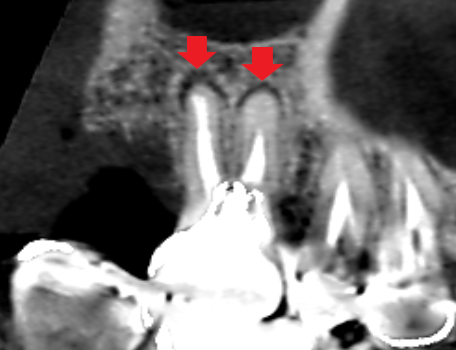

上顎第一大臼歯の冠状断のCT画像です。

赤い矢印の先の近心頬側根に膿の影がみられます。近心頬側根には、青い矢印の先に黒い線が認められ、未治療の根管があります。近心頬側根の膿は未治療の根管が原因と思われます。